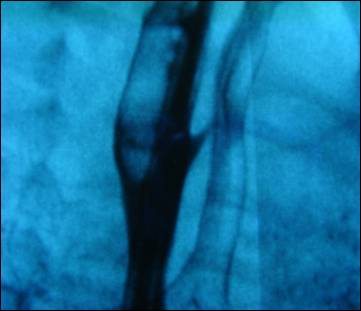

unremarkable. With high suspicion of H-type TEF, a tube esophagram was

performed which showed contrast flowing into tracheobronchial tree through a

fistula between trachea and esophagus at the level of T1 (Fig.1,2).

Figure 1: Tube esophagram showing a

contrast within the tracheobronchial tree suggestive of TEF.

Figure 2: Negative macro image of

esophagram delineating fistula between trachea and esophagus